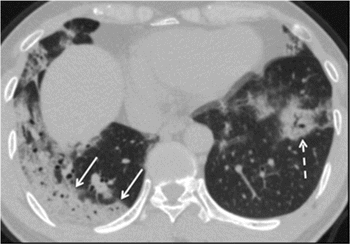

Patients with the coronavirus who develop pneumonia exhibit similar findings on chest CT scans.